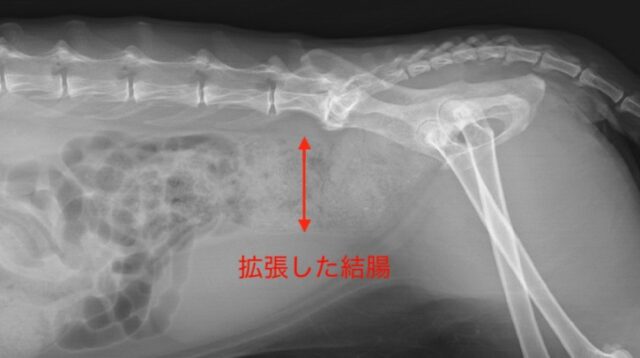

特に猫では、慢性的な便秘が「巨大結腸症」と呼ばれる病態につながることがあります。(以下は猫のレントゲンの画像です)

身体検査で腹部の触診で硬い便の有無を確認し、レントゲン検査で便のたまり具合や骨盤、腸の形態を評価します。また原因疾患の精査のために血液検査や超音波検査を実施します。